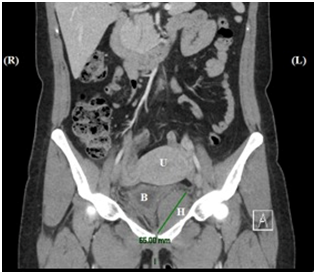

Pelvic examination revealed 30-50cc of blood in vaginal vault, with no active bleeding from vaginal mucosa and suture lines noted to be intact. Vital signs and labs were within normal limits other than hemoglobin/hematocrit (8.1/23.5) noted to be stable since prior admission for the surgery. The patient underwent a computer tomography (CT) scan of the abdomen and pelvis. Imaging revealed a hematoma in the left obturator musculature measuring 6.5 x 4.0 x 4.7cm with mass effect on the bladder (Figure 1) (Figure 2). The patient was able to void without difficulty despite this mass effect. Given that vitals were stable, and her symptoms subsided after hydration and analgesia, decision was made to discharge patient with close outpatient follow-up. The patient was asymptomatic at subsequent visits 3-4 months following surgery, and no further intervention was required.

Figure 1Coronal view of hematoma (H) in the left obturator region measuring 6.5cm in length with mass effect on the bladder (B), displacing it to the right. Uterus (U) is superior to both the bladder and hematoma. (R), right; (L), left.